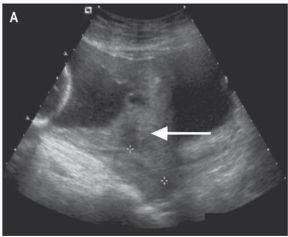

△

箭头指的正常子宫肌层的回声带缺失,胎盘侵入了子宫肌层。